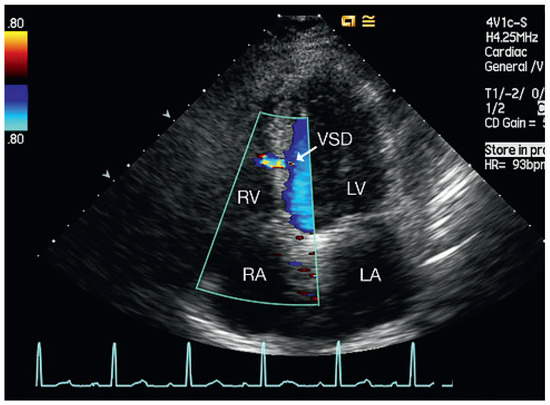

Muscular Ventricular Septal Defect After Mitral and Aortic Valve Replacement

by Augusto Aragão, Dorothea Vogel and Christoph Schmidt

Cardiovasc. Med. 2010, 13(5), 167; https://doi.org/10.4414/cvm.2010.01500 - 26 May 2010

We describe a case series of five patients who were referred to our cardiac rehabilitation department after mitral or aortic valve replacement, and whose transthoracic echocardiographic studies showed postoperative muscular septal defects. Full article

Show Figures

Figure 1